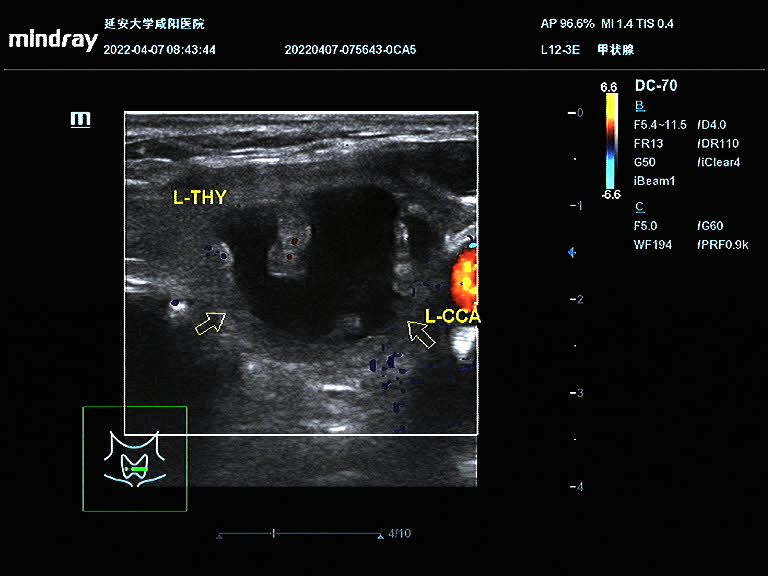

王女士在半年前因頸部包塊就診于我院,超聲提示甲狀腺左葉囊實性包塊,因疫情原因未進一步治療;近半年來包塊明顯增大,頸部膨隆,為進一步治療就診于我院血液內(nèi)分泌科。彩超診斷為甲狀腺左側(cè)葉囊實性結(jié)節(jié),患者因懼怕疼痛,不愿手術(shù),選擇保守治療;后得知甲狀腺結(jié)節(jié)可以超聲引導(dǎo)下微創(chuàng)治療,遂聯(lián)系超聲科進行咨詢;超聲科醫(yī)生對王女士的甲狀腺結(jié)節(jié)進行評估后,就射頻消融術(shù)的優(yōu)點、術(shù)前的準(zhǔn)備、術(shù)中的風(fēng)險、術(shù)后的注意事項詳細(xì)講解,王女士當(dāng)即決定選擇射頻消融術(shù)治療甲狀腺結(jié)節(jié)。4月9日下午在介入超聲手術(shù)室順利完成手術(shù),術(shù)后頸部僅一個針眼大小。術(shù)中囊性部分抽吸為黑紅色粘稠液,實性部分消融治療,術(shù)后即刻造影結(jié)節(jié)內(nèi)未見造影劑回聲。

術(shù)前結(jié)節(jié)大?。?4.9mm×31.8mm×22.2mm